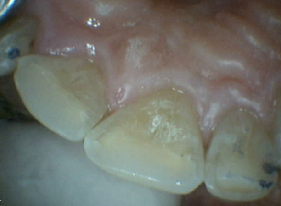

Zirconia Anterior Crowns